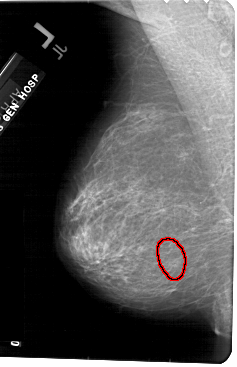

A_1562_1.LEFT_CC

LEFT_CC LINES 5491 PIXELS_PER_LINE 3301 BITS_PER_PIXEL 12 RESOLUTION 43.5 OVERLAY

FILE: A_1562_1.LEFT_MLO.OVERLAY

TOTAL_ABNORMALITIES 1

ABNORMALITY 1

LESION_TYPE CALCIFICATION TYPE AMORPHOUS DISTRIBUTION CLUSTERED

ASSESSMENT 4

SUBTLETY 3

PATHOLOGY BENIGN

TOTAL_OUTLINES 1